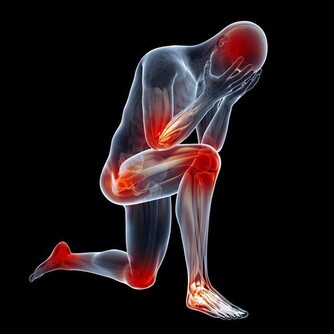

*****一、當血​​管變硬時,腿腳會發出4個信號*****

***(二)腿腳莫名的疼痛***

如果腿部血管出現硬化,那麼最明顯的表現就是莫名疼痛。可能一些輕微的血管硬化,在我們行走時會出現痛感,如果稍作休息就會有所緩解,但是一些程度比較嚴重的血管硬化,它的痛感非常明顯,如果放任不管,最終就會形成間歇性跛行。

***(三)腿腳腫脹發麻***

血管有硬化的趨勢時,人體的血液流動速度就會受到影響而變得緩慢,不​​加以控制就會導致腿部得不到足夠的氧氣以及養分,所以才會出現腫脹發麻。當然這种血管堵塞,一般情況下會出現單側堵塞。

***(四)手腳莫名冰涼***

很多人到了冬天就會出現手腳冰涼,當然這也是非常常見的現象,畢竟冬天氣溫低,整個人都感覺非常冰冷。如果是血管硬化堵塞的人,那麼他不管是春夏秋冬,一年四季均有可能出現手腳冰涼,最終導致手腳不能得到足夠的血液供應,所以才會出現手腳冰涼,如果你觀察自己的雙手雙腳血色飽滿,常年暖乎乎的,說明血管還是非常不錯的。